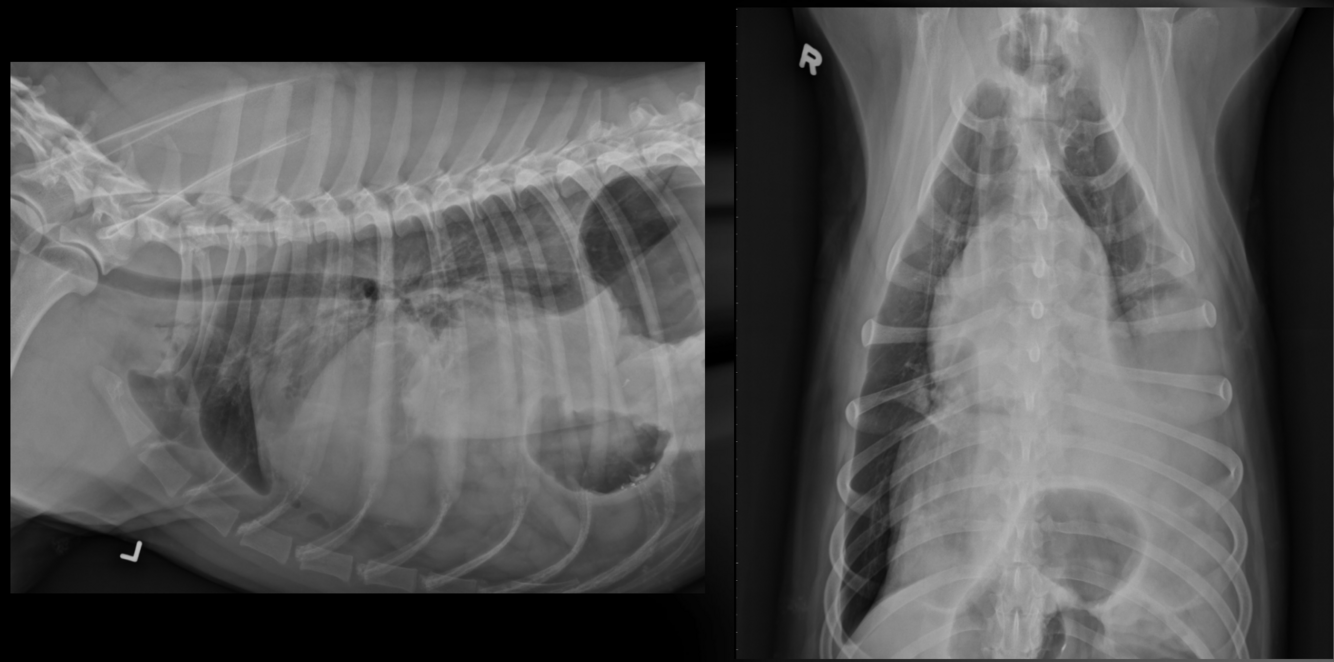

What is important regarding the ribs in these radiographs?

middle-aged dog; costal cartilages have mineralized but not excessively

old dog; costal cartilages show irregular, exuberant mineralization